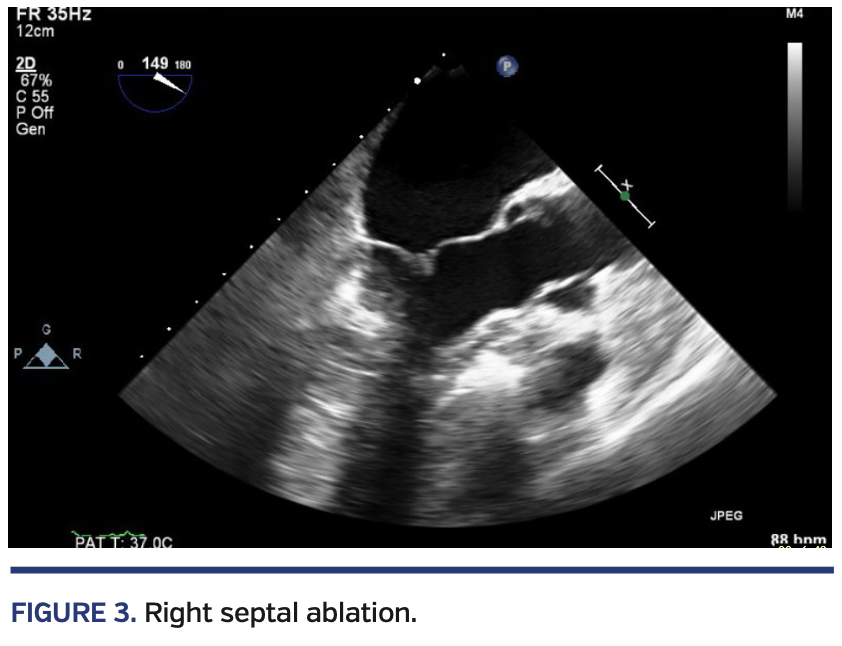

Via an RCA guiding catheter, a coronary wire was then advanced into the RCA and an over-the-wire balloon was advanced into the septal perforator. Contrast injection showed echocardiographic enhancement of a more apical segment of the septum (Figure 3). Additional alcohol was administered after the balloon was inflated. Final Doppler echocardiography showed reduction of left ventricle-aorta pressure gradient to 5 mm Hg, which was consistent with catheter gradient (Figure 4). Mitral regurgitation appeared mild and SAM was resolved.